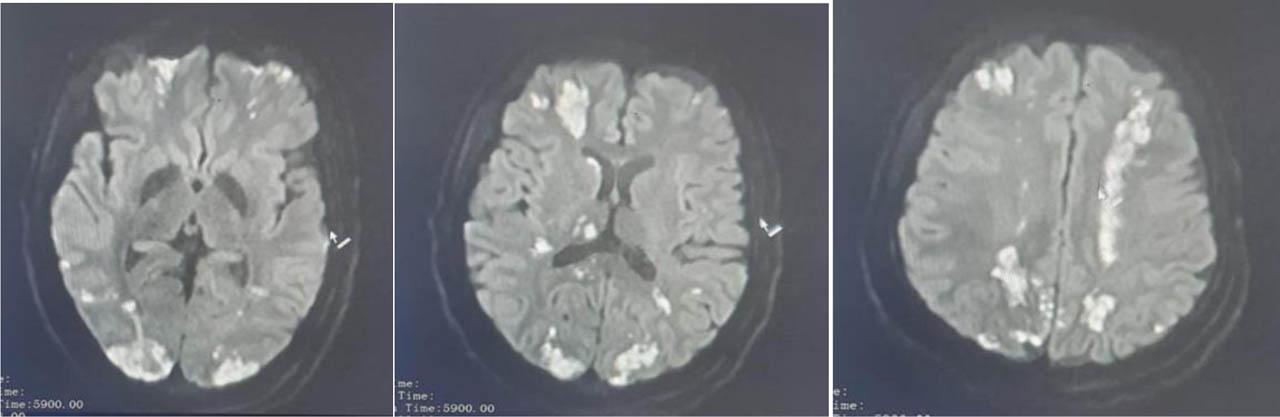

Figure 1,2, 3.